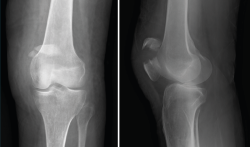

1.1.1. Fémur (Figura 1)

Figura 1. Radiografías anteroposterior y lateral de rodilla: fractura longitudinal del fémur extendida a la articulación.